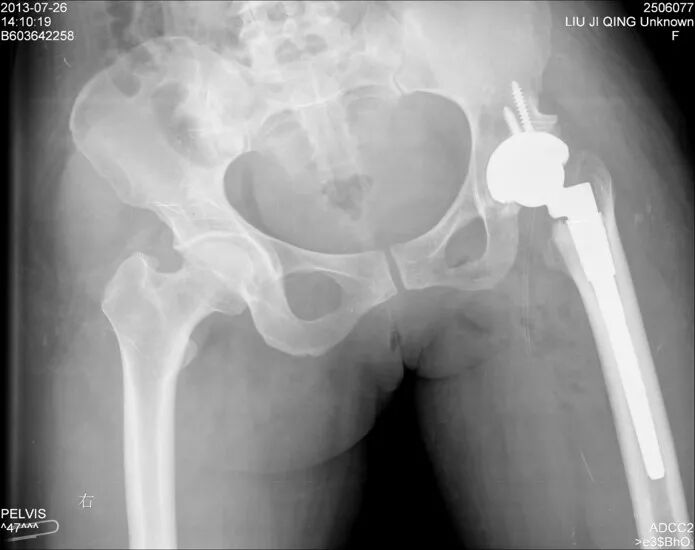

切开复位

术后4月,再一次脱位

术后股骨头旋转中心点增高,导致患肢延长